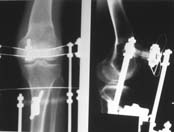

Пациент В. 53 лет, травма в феврале 2009. ДЗ. Открытый оскольчатый перелом нижней трети голени. При боли поступлении выполено ПХО, аппарат Илизарова. В последующем проводили ВХО, резекция костных отломков, укорочение 6 см, рана зажила. Была выполнена остеотомия большеберцовой кости в проксимальном отделе, резекция. Производилось тракция. На последних рентгенограммах выявлено, что одновременно с "выращиванием" регенерата произошло низведение надколенника на длину выращенного регенерата. Клинически: активное разгибание сохранено, объем движений в колене 180-110 градусов. Черными стрелками обозначен верхний край надколенника с одной и с другой стороны. Красная стрелка обозначает пальпируемую связку надколенника. Причина - остеотомия выше места прикрепления связки надколенника. Вопрос: была ли у кого подобная ситуация? Что делать? При первом обдумывании приходит решение: отсечение места прикрепления связки надколенника с костным блоком, перемещение на "правильное" место, укорочение сухожилия четырехглавой мышцы.

По-моему, надколенник низвелся на величину, гораздо меньшую удлинению.

Я бы уменьшил диастаз между фрагментами сантиметра на два. Судя по снимкам, регенерат это может позволить.